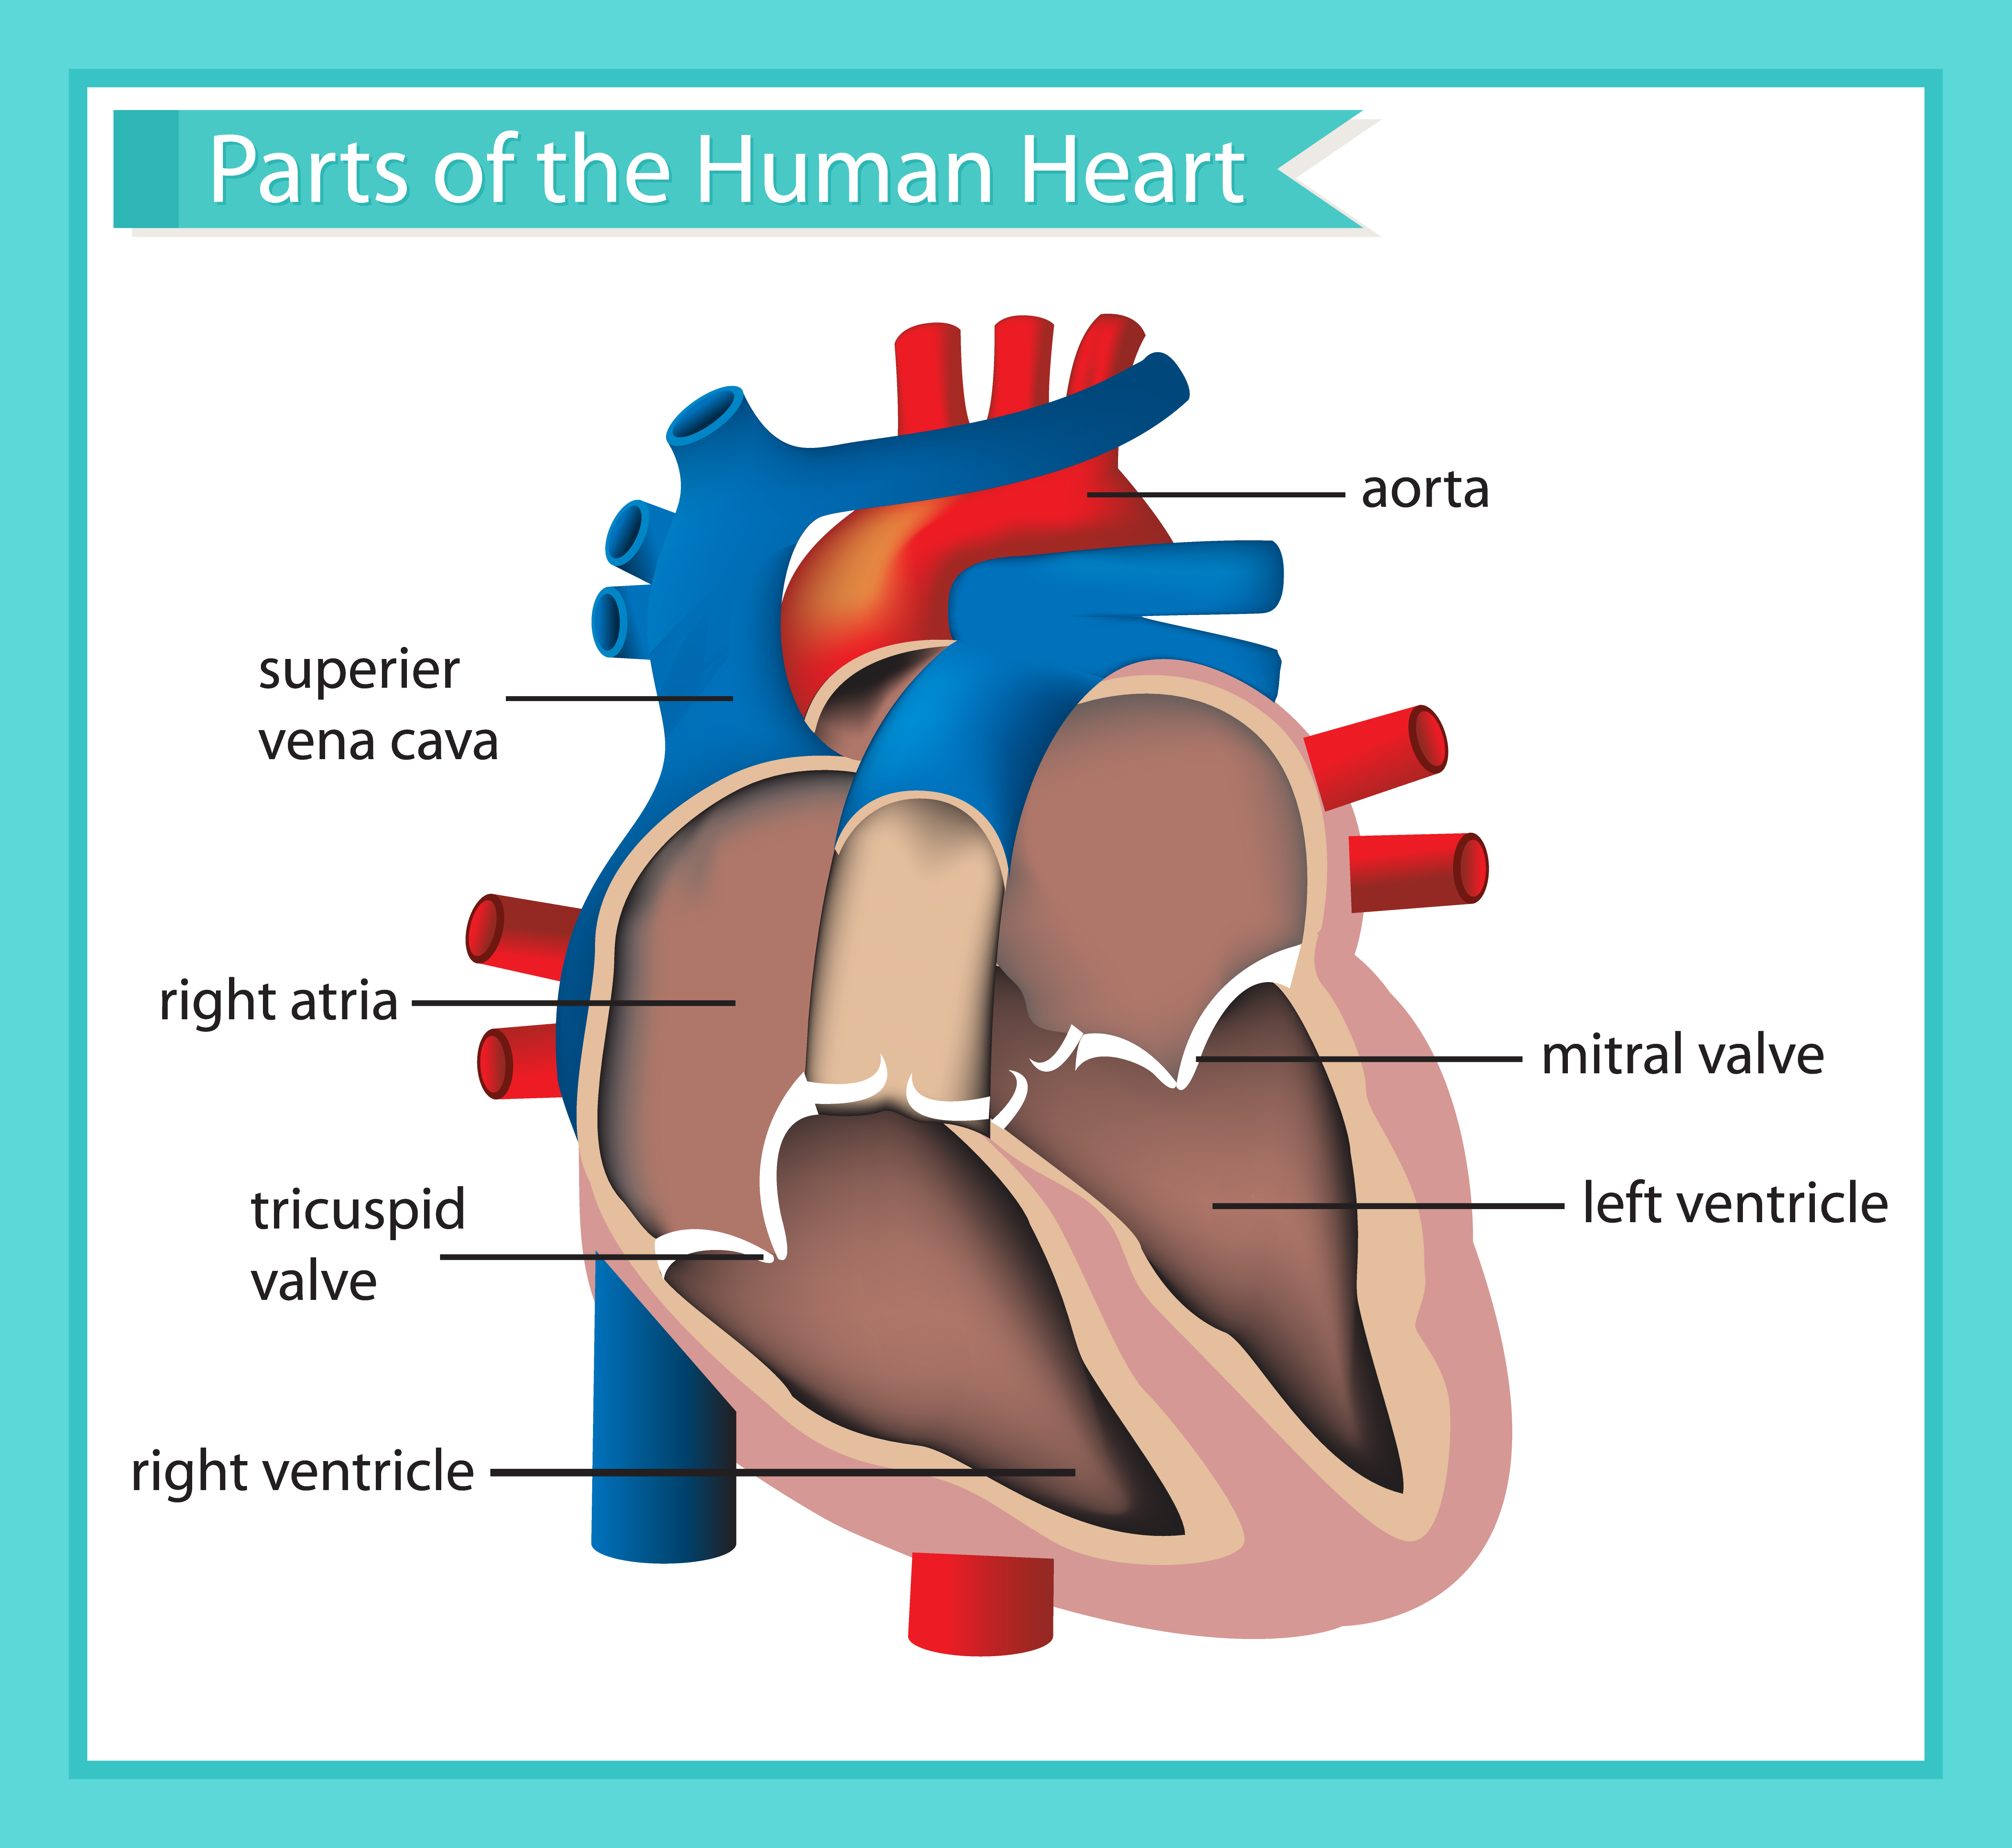

What are the parts that make up a human heart? Diagrams and More | Human heart diagram, Heart

What are the parts that make up a human heart? Diagrams and More | Human heart diagram, Heart  Human heart by kortney16 on DeviantArt

Human Heart Diagrams | 101 Diagrams  Human Heart Simple Drawing at GetDrawings | Free download

Anatomy of the Heart: Physiology | Health Life Media  Human Heart Anatomy Drawing at GetDrawings | Free download

Human Heart - Circulatory System | OER Commons  de Location Of Human Heart In Body mar webmds heart anatomy page provides a detailed image of

Scientific medical illustration of parts of the human heart 685453 Vector Art at Vecteezy  Human Heart Drawing Outline at GetDrawings | Free download

Anatomy of the human heart  Human Heart Drawing Line Work stock vector art 481404348 | iStock